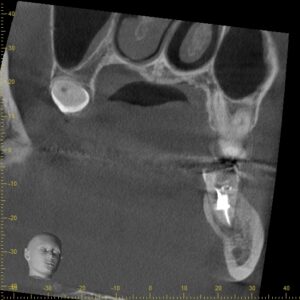

3方向から見た画像です。

下の奥歯の周囲が黒く抜けているのが分かるでしょうか。

通常歯の根は骨に覆われているため、根の周囲が白く見えます。

この部分は菌により骨が溶けてしまい骨の硬さが弱くなることでレントゲンで黒く見えてきています。

この状態になっていると神経を取る治療、根管治療が必要になります。